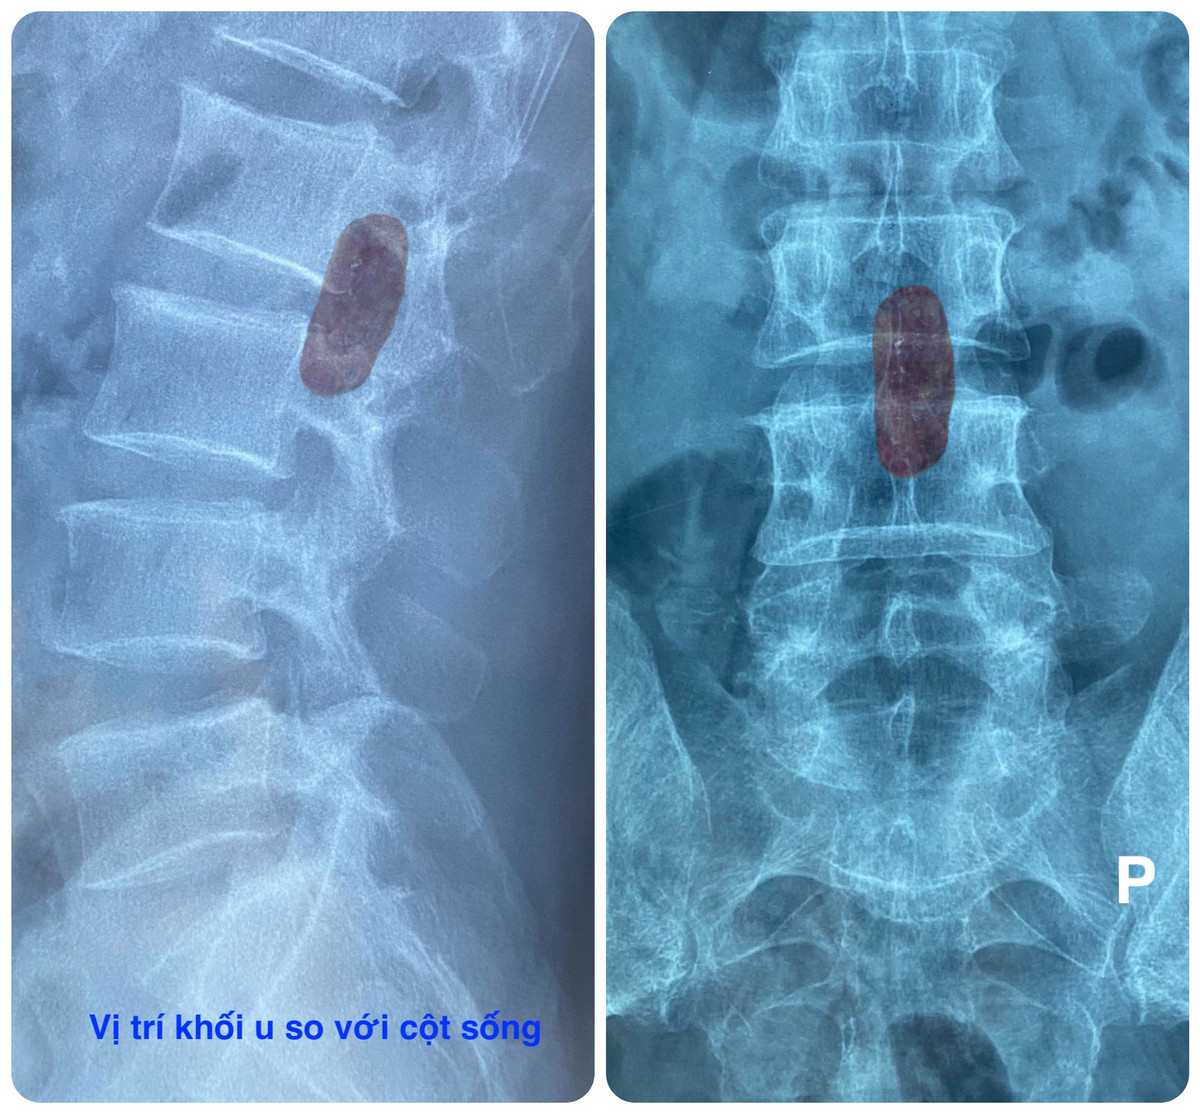

Sau khi thăm khám và chụp MRI cột sống thắt lưng, các bác sĩ nghi ngờ bệnh nhân bị u bao sợi thần kinh cột sống (Schwannoma) với kích thước khá lớn.

Khối u gây chèn ép chùm đuôi ngựa. Do vậy, các bác sĩ Bệnh viện Hoàn Mỹ ITO Đồng Nai quyết định phẫu thuật bóc tách khối u. Bởi, nếu để u phát triển quá to sẽ chèn ép thần kinh, có thể gây liệt hai chân, rối loạn đại tiểu tiện.